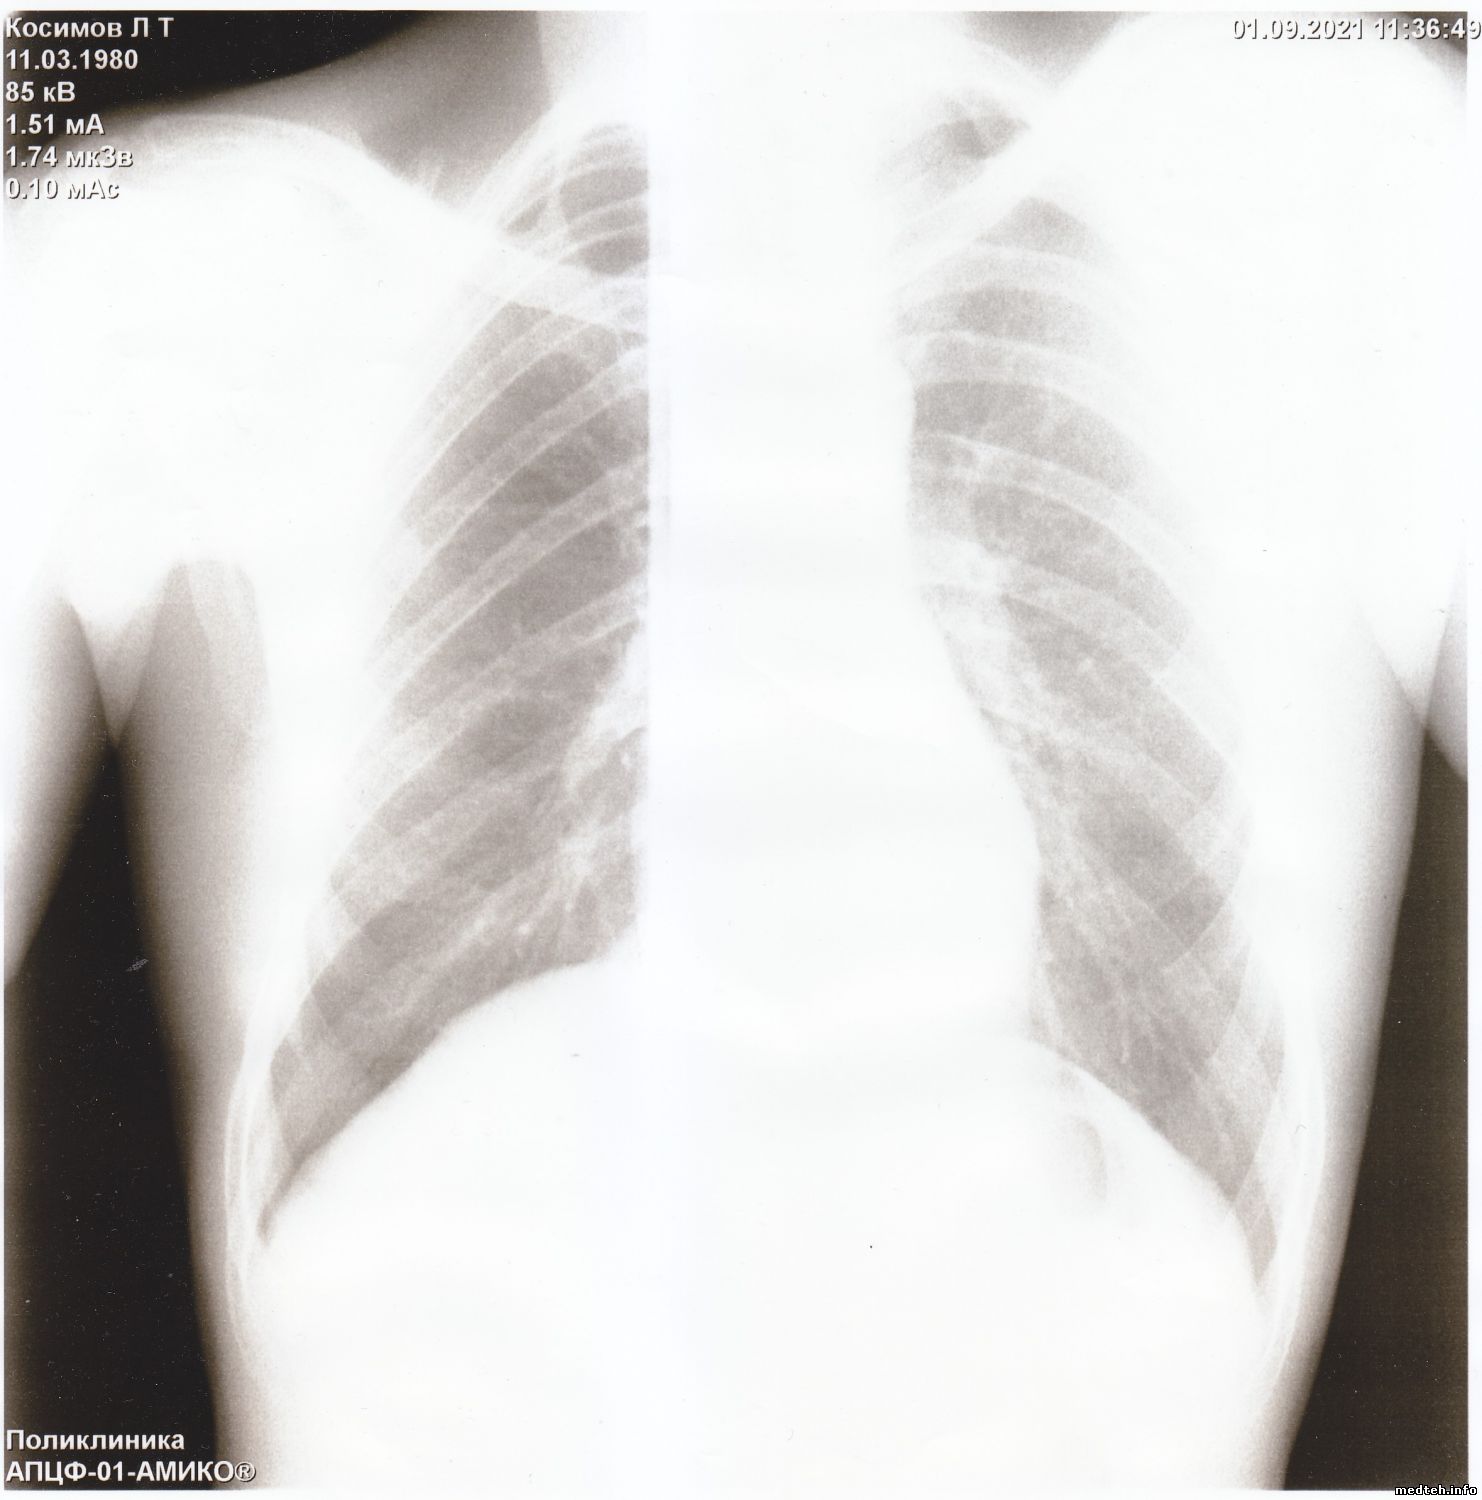

Здравствуйте коллеги.

Прислали снимки из другого города, просят помочь устранить неисправность.

Аппарат я не видел. По снимкам, конечно, не установишь причину, может у кого была такая проблема.

Появились горизонтальные и вертикальные полосы на снимках, делает снимки - смещённые на половину. Снимок есть, видны легкие и все остальное, но полосы очень мешают докторам.

Подскажите что можно сделать в данной ситуации.

Друзья, думаю, вы знаете решение этой проблемы.

Фото прилагается.

Всё решилось просто - тренировка - калибровка и нормальные снимки.